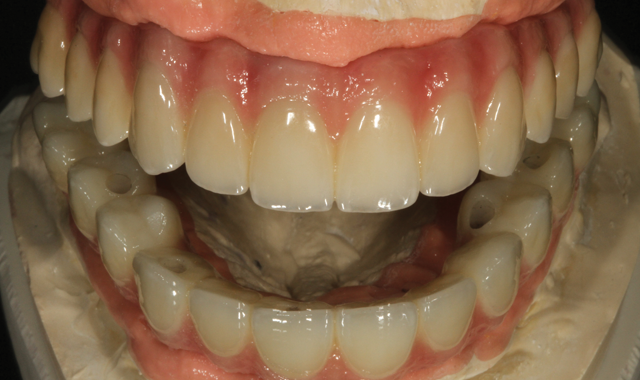

Fig. 15 Wax try-in

A wax try-in model is compared to the final restoration, after duplication (Fig. 15) to verify fit and appearance based on the beginning stages.

Fig. 16 Try-in the mouth

Final, upside down view of the six implant units (Fig. 16) follow.